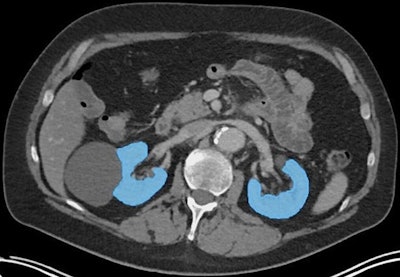

An axial CT image illustrating segmentation of functioning kidney tissue (blue areas), excluding kidney cysts and renal pelvis, using TotalSegmentator. Image and caption courtesy of RSNA.An axial CT image illustrating segmentation of functioning kidney tissue (blue areas), excluding kidney cysts and renal pelvis, using TotalSegmentator. Image and caption courtesy of RSNA.

The tool automatically segments total kidney volume on standard CT images, with measurements predicting deterioration of renal function 12 months after patients initiated therapy, noted lead authors Lisa Steinhelfer, MD, and Friederike Jungmann, MD, of the Technical University of Munich in Germany, and colleagues.

To address the knowledge gap, the investigators retrospectively analyzed data from 121 patients who underwent CT scans and four or more cycles of Lu-177 PSMA-I&T therapy over a year period. They extracted total kidney volume (TKV) from images at three and six months after treatment using an AI tool called TotalSegmentator, a freely available segmentation AI model developed by a Swiss team in 2023.